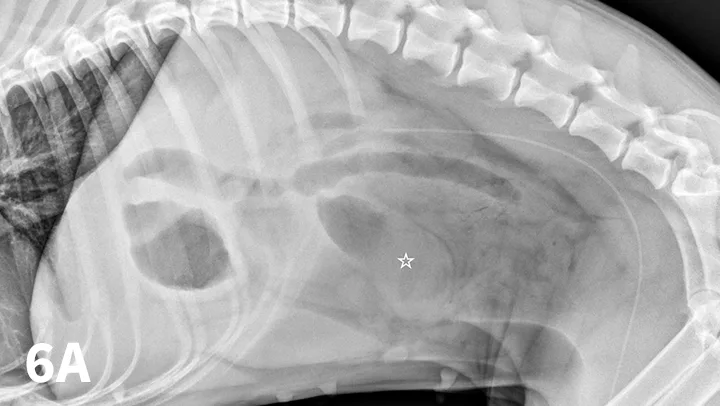

FIGURE 3A

Left lateral radiograph of a 4-year-old crossbreed dog with a history of vomiting. The patient was clinically stable. Granular, well-defined soft tissue opaque material is present within the fundus of the stomach, consistent with food or foreign material.